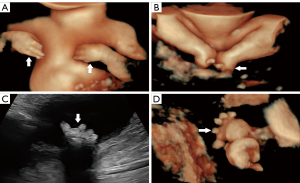

Ultrasonography at our institution revealed the following: Bilateral lateral ventriculomegaly, with a left ventricular width of 47 mm and a right ventricular width of 23 mm (Figure 1A), and a “dumbbell-shaped” moderately echogenic mass (26 mm × 15 mm) anterior to the fetal trachea, encircling the airway with homogeneous internal echogenicity. Color Doppler flow imaging showed no significant vascularity in the central portion of the mass but sparse flow signals peripherally (Figure 1B-1D, and Videos 1,2). Three-dimensional surface rendering confirmed anterior cervical swelling (Figure 1E), a narrowed fetal thoracic cage (transverse thoracic diameter: 48 mm) with an increased cardiothoracic ratio (cardiac transverse diameter: 32 mm), and a ventricular septal defect (2.5 mm) (Figure 1F). Persistently extended upper limbs and a fixed cross-legged lower limb posture without dynamic changes were also observed (Figure 2A,2B and Video 3). The metatarsal bones were poorly visualized, with only phalanges identified in both feet (Figure 2C,2D, and Video 4). The amniotic fluid assessment showed a maximum vertical pocket depth of 106 mm and an amniotic fluid index of 368 mm. The ultrasonographic diagnosis was as follows: (I) severe fetal hydrocephalus; (II) an anterior cervical hyperechoic mass, suggestive of thyroid goiter; (III) a narrowed thoracic cage with increased cardiothoracic ratio and ventricular septal defect; (IV) metatarsal hypoplasia and fixed limb postures; and (V) moderate polyhydramnios. Prenatal umbilical vein puncture confirmed fetal hypothyroidism (TSH: 11.32 mU/L; normal range, 0.38–4.34). The family opted to terminate the pregnancy at an external institution, as in addition to the fetal malformation, the patient was unmarried, and the pregnancy unplanned. Documentation provided by the family indicated that the autopsy findings were consistent with our ultrasound diagnoses, though post-procedure images were unavailable.